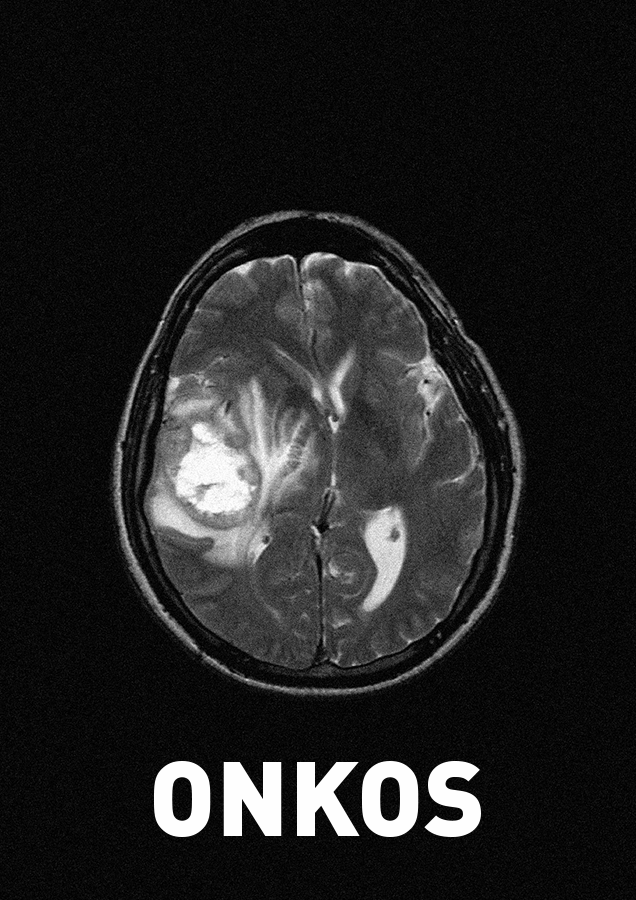

Le livre qu’il m’a confié, ONKOS, est rare et bouleversant.

Composé de photographies faites au téléphone portable, dans un hôpital, durant le dernier mois de vie de son père, c’est un livre de deuil et d’amour qui interroge l’impossible de la disparition d’un proche dont la vie se retire parmi le langage muet des choses qui l’entourent.

Il faut beaucoup de courage pour montrer ces images, qui sont, malgré la peine et l’insoutenable, un hymne aux liens d’attachement les plus fins, les plus forts, les plus infinis.

Vous avez publié aux ateliers OOBLIK un livre très intime et bouleversant sur la mort de votre père, ONKOS, Voir son père pleurer, ensemble d’images prises avec un téléphone portable pendant le dernier mois de vie de votre père, victime d’un cancer, à l’hôpital (04/03/2018 – 03/05/2018). C’est un livre de deuil et d’amour. A-t-il été facilement accepté/compris par vos proches ?

Je vais avoir plus de mal à décrire ici ce que je n’ai pu faire qu’avec des images. C’est encore trop présent pour avoir un début de réflexion. J’ai fait ces images dans l’urgence, celle de garder un peu de mon père, et, pour être franc, je n’ai même pas montré ONKOS à toute ma famille, et je ne l’ai pas fait pour savoir si j’avais ou non leur assentiment, absolument pas, je l’ai fait pour lui, pour mes enfants, pour moi. Il faudra du temps pour que ces images ne soulèvent plus de larmes, là aussi il faut de la lenteur. J’ai du mal à le re-regarder aujourd’hui, comme un détachement entre ces moments où j’avais comme l’obligation de capturer le vivant entre lui et moi, et comme la sensation de n’avoir plus qu’un vide, un silence dans ces images maintenant.

On voit aussi sur le mur de la chambre le dessin d’une voiture envoyé par un enfant, tandis que la pluie pleure sur les vitres de l’hôpital. ONKOS se découvre avec lenteur, dans un infini respect. Il ouvre sur le mystère de la vie, de la mort, interrogeant la présence ou l’absence de dieu, le fini, l’infini. Votre père a-t-il compris que vous construisiez pour lui, pour vous, pour votre famille, un livre de secours ?

Non, la réponse la plus courte de votre questionnaire, parce que vos mots sont plus justes et pertinents que ce que je pourrais rajouter. Mon père n’a rien vu de mes photos de lui, je ne me suis pas caché pour autant, mais j’ai toujours été discret. J’ai eu beaucoup de silence avec lui, c’est un tel mystère la maladie, un tel abyme que de connaître l’issue, j’ai eu beaucoup de mal à exprimer toutes ces émotions devant lui, me prenant même à lui dire que tout espoir de guérison sur son cancer n’était pas impossible ; comment ne pas avoir envie de mentir ? Il est parti le lendemain de la fête des pères, nous avons pu l’entourer jusque-là. J’ai fait des images ce jour et les jours d’après, je ne sais pas si je pourrai les regarder sereinement un jour, les monter sous quelque forme que ce soit, mais elles existent, et je reprendrai pour finir votre belle formule, comme une bouée de secours.

Marc Tallec, Onkos, Voir son père pleurer, 2018 – ateliers OOBLIK, 100 exemplaires numérotés